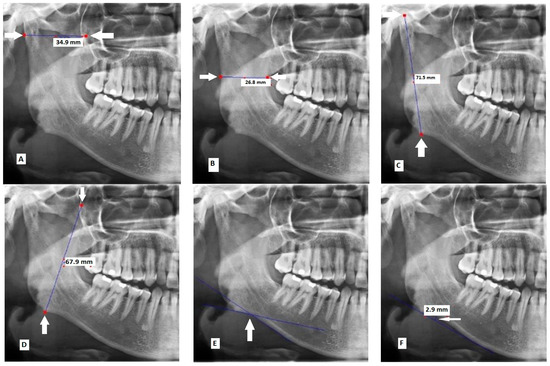

- Maximum ramus width: Maximum anteroposterior ramus width (Figure 1A) [16].

Figure 1. Measurements made on panoramic radiographs: (A) maximum ramus width; (B) minimum ramus width; (C) condylar height; (D) coronoid height; (E) antegonial angle; (F) antegonial depth; (G) gonial angle; (H) distance between the superior border of the mental foreman and the inferior border of the ramus; (I) distance between the inferior border of the mental foramen and the inferior border of the ramus; (J) bicondylar breadth; and (K) bigonial breadth. - Minimum ramus width: Minimum anteroposterior ramus width (Figure 1B) [16].

- Condylar height: Distance between the most superior part of the condyle and the most inferior part of the inferior border of the body of mandible (Figure 1C) [19].

- Coronoid height: Distance between the most superior part of the coronoid process and the most inferior part of the inferior border of the body of mandible (Figure 1D) [20].

- Antegonial angle: Intersection of two lines at the deepest point of the inferior border of mandible. The first line passes through the anterior part of the inferior border of mandible and the second line passes through the inferior border at the gonion (Figure 1E) [21].

- Antegonial depth: Vertical distance between the inferior border of the mandible and its deepest point (Figure 1F) [21].

- Gonial angle: Angle formed between the following two lines: A line tangent to the ramus and the mandibular condyle, and a line tangent to the most inferior part of the gonial section and the body of the mandible (Figure 1G) [18].

- Distance between the superior border of the mental foramen and the inferior border of the ramus (Figure 1H) [22].

- Distance between the inferior border of the mental foramen and the inferior border of the ramus (Figure 1I) [23].